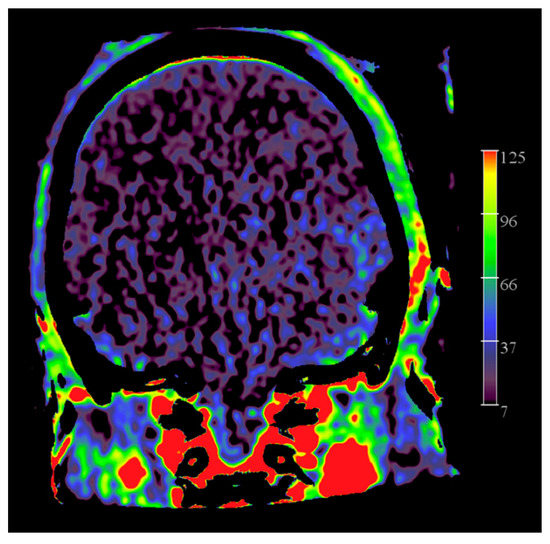

- O’Connor, K.P.; Milton, C.K.; Strickland, A.; Apple, B.; Bohnstedt, B.N. Flat-Detector CT to Quantify Response to Intra-Arterial Spasmolytic Therapy for Cerebral Vasospasm. J. Neuroimaging 2020, 30, 227–232. [Google Scholar] [CrossRef]